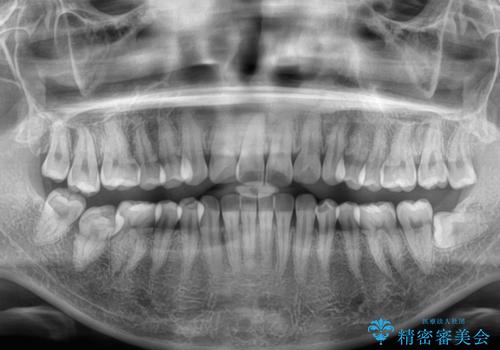

- 上下前歯のデコボコを気にして来院された患者様です。

ワイヤー矯正でもマウスピース矯正でも可能でしたが、短期間で、自身の手を煩わせることなく治療を行いたいとのことで、ワイヤー装置にて矯正治療を行うこととしました。

舌の突出癖により、出っ歯仕上がりとなる可能性がありましたが、舌のトレーニングを頑張っていただき、1年強で終えることができました。